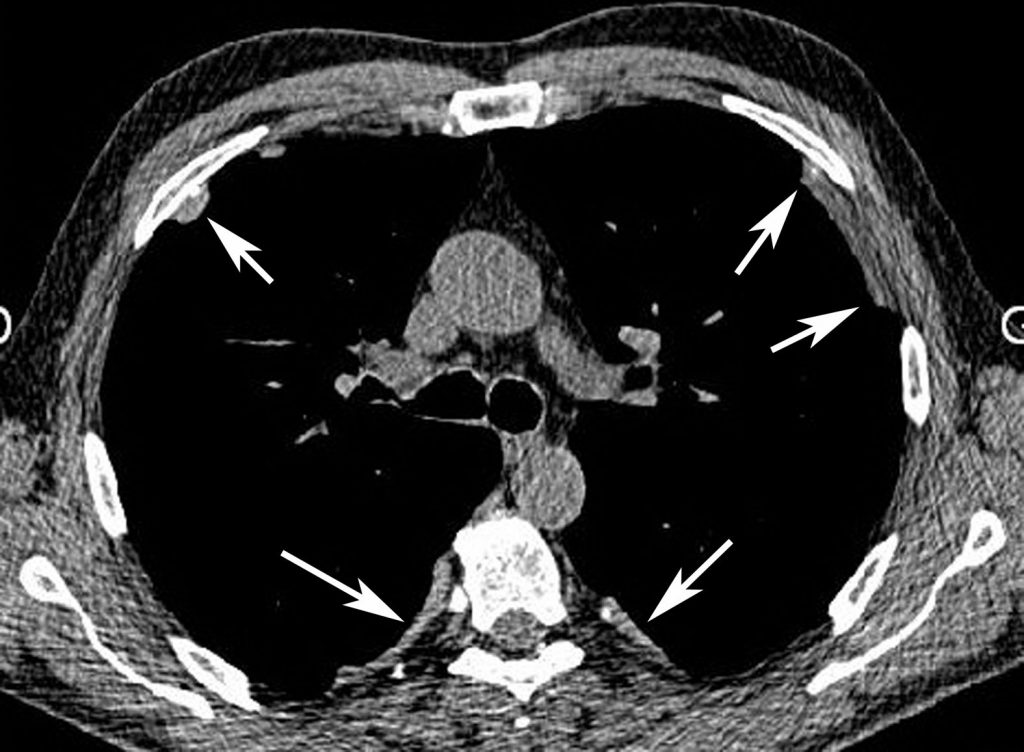

Fig. 95.2. Plaques pleurales en scanner.

Surélévations quadrangulaires pleurales en plateau, de densité tissulaire à bords nets (flèches) au niveau de la paroi antérolatérale du thorax et de la gouttière costovertébrale.

Source : CERF, CNEBMN, 2022.